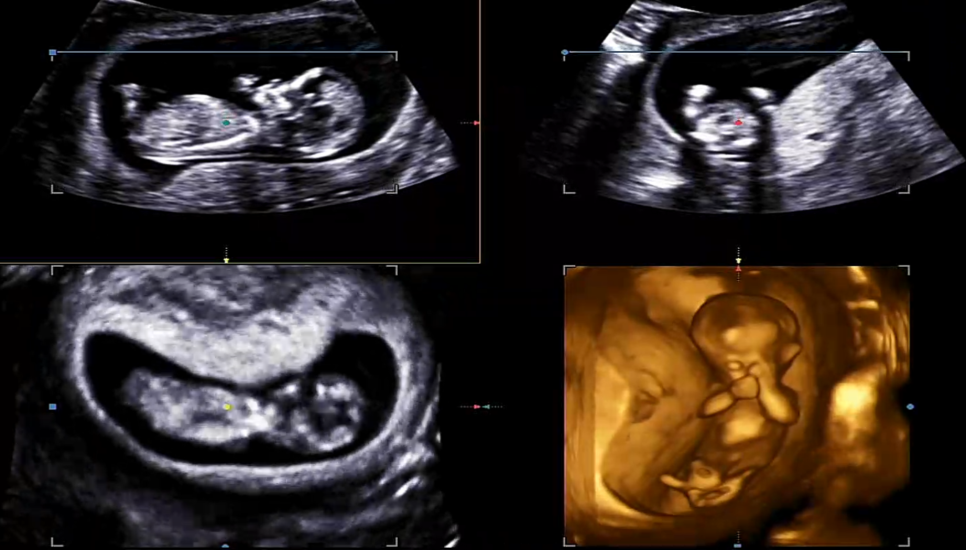

1차 초음파 검사에서는 입체 초음파를 봅니다입체로 아기의 모습을 찍어 줍니다만, 입체로 변환되면 오히려 잘 보이지 않아요.#입체초음파요즘은 살색처럼 나오는 곳도 많은데 여기는 약간 황금아기처럼 ㅋㅋㅋㅋㅋㅋㅋㅋㅋㅋㅋㅋㅋㅋㅋㅋㅋㅋ

손이 얼굴 앞에서 알찬 모습이었어요입체 초음파를 봤는데 역시 막무가내? 보여서 잘 안 보였어요 ㅎㅎㅎ

손으로 눈을 문지르는 듯한 모습 ㅋㅋㅋ

1차 기형아 검사 입체 초음파 리뷰~

12주 입체 초음파~